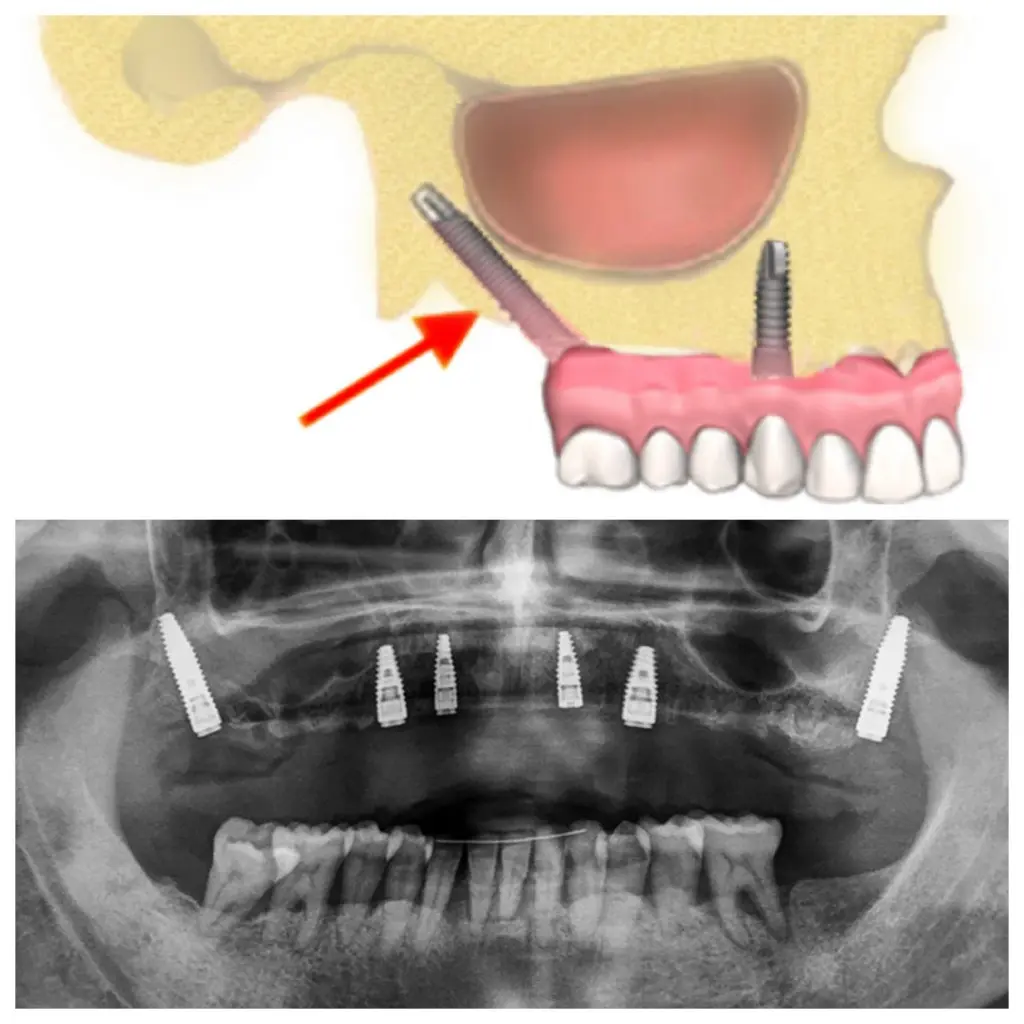

La sedación consciente en odontología es un método revolucionario que tan sólo se lleva a cabo en clínicas especializadas como en nuestras clínicas de Bilbao y Donostia. Se utiliza, sobre todo, en intervenciones de implantes dentales, y en implantes dentales en un día.

Implantes dentales pterigoideos

Cirugía guiada implantes

Implantes inclinados